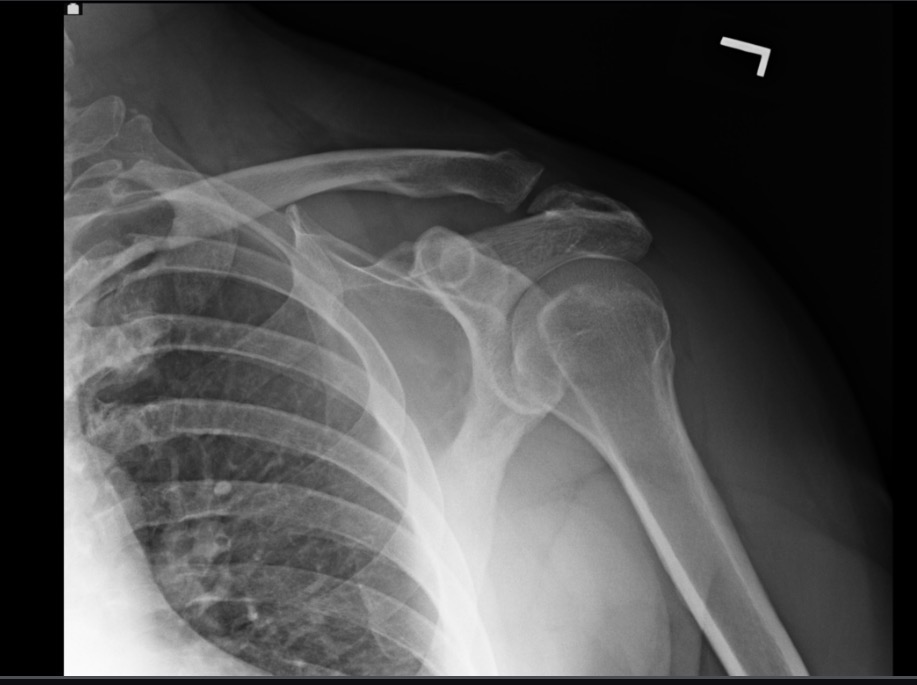

What projection position is this image?

AP LPO Grashey, left